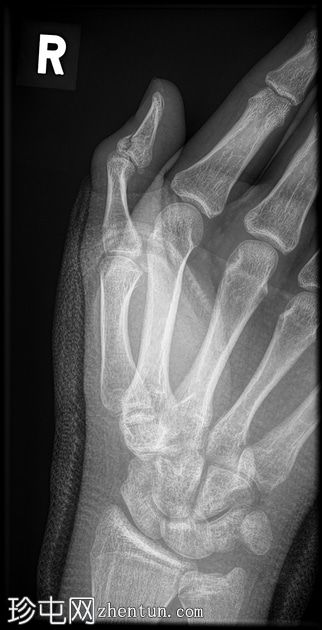

斜位片

玻璃纤维拇指人字形石膏固定。

舟骨腰部骨折合并骨折。

第一近节指骨背侧基底部急性关节内骨折。

这位患者很不幸——舟骨骨折几乎已经痊愈,却因摔倒导致拇指远端指骨再次骨折。当然,拇指人字形石膏固定并没有起到作用,反而可能由于近节关节活动范围减小而导致撕脱性骨折。